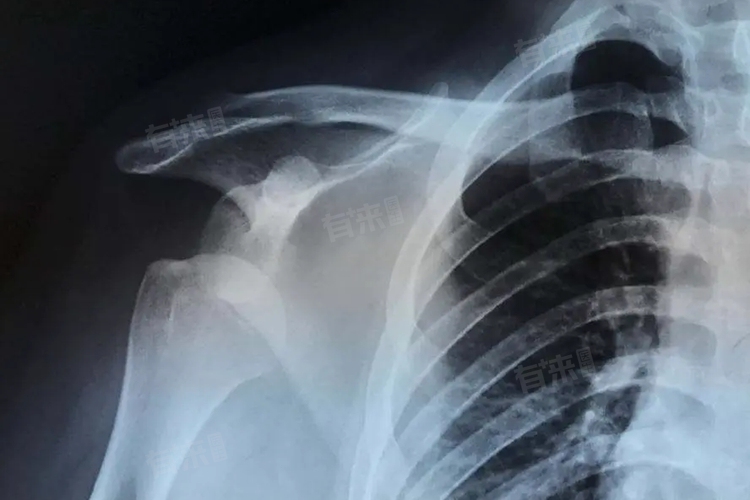

肩关节半脱位发生原因多种多样,如肌肉韧带退行性变、外伤等,一旦患者出现相关症状,应及时前往医院的骨科或运动医学科就诊,以便医生通过详细的体格检查和影像学检查,如X光片、CT扫描或MRI等,明确诊断并制定合理的治疗方案。

4、骨折:

肩部骨折,如肩峰骨折或肩胛骨骨折,可能导致肩关节的正常解剖结构发生改变,进而影响其稳定性。骨折端移位可能压迫周围的神经血管束,导致血液循环受阻,进一步加剧肩关节半脱位的风险。骨折引起的半脱位通常需要通过手术治疗来恢复肩关节的稳定性。